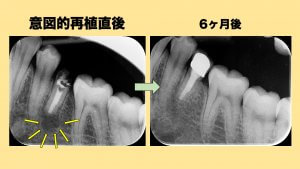

意図的再植術

今回はオトガイ孔の近接のため歯根端切除術よりも意図的再植術を選択しました。

歯の根っこの周りには歯根膜と言う組織があります、一度抜いてもこの歯根膜がきれいに保存されていれば高い確率で再度植え直しても生着します。

この歯根膜を利用して抜いてから悪くなった病変を除去することができるわけです。

今回は術後の経過も良好でフィステルも消失し根尖部の透過像も綺麗に消失しているので一安心です。